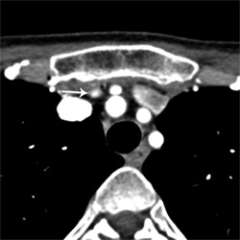

Figure 4a. Parathyroid 4D-CT showing multiple gland hyperplasia in the same patient, missed in a prior surgery. Enlarged right inferior parathyroid gland, below the right thyroid lobe.

Figure 4b. Parathyroid 4D-CT showing multiple gland hyperplasia in the same patient, missed in a prior surgery. Enlarged right superior parathyroid gland, next to the esophagus.